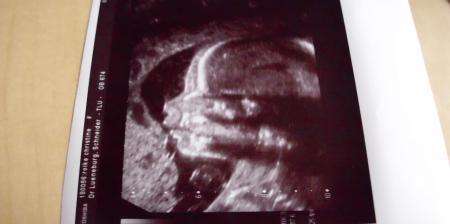

jetzt ist es 100%ig. unser drittes kind wird ( auch) ein mädchen mein gefühl hat mich völlig getrügt.... hatte ja heute fein-us und da sah man es. ansonsten ist alles supi. menne findet das gut, er meinet es weiß ja wie man mit kleinen zicken umgeht lg christine mit finja, mathilda und sophia inside

ich hatte heute doch ein bißchen muffensausen, aber als herz und gehirn ok waren, war ich völlig ruhig. das war mir das wichtigste. oh mann, drei mädels, ich kanns noch garnicht richtig glauben...

Tolles Foto!!! Danke fuer's Posten! Und ja: Ich hatte letzte Woche auch ziemlich muffe vor der FD! Geniess das Gefuehl der Erleichterung und der Freude von ganzem Herzen!! GLG Agi